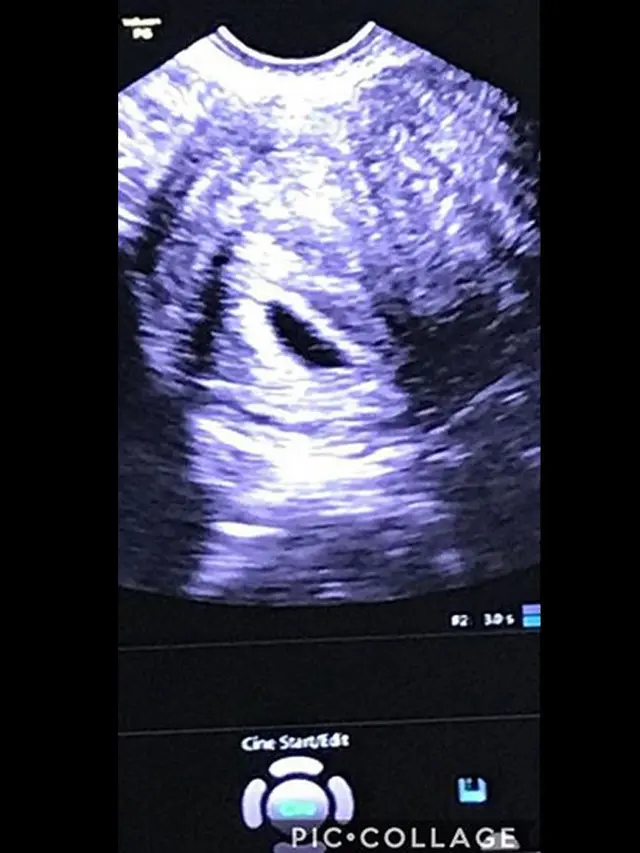

Walaupun belum genap tiga bulan janin berkembang di dalam perutnya, Kalina yakin kalau jabang bayi dalam kandungannya itu berjenis kelamin wanita. Wanita berparas cantik itu ternyata sudah menyiapkan untuk calon buah hatinya.

Kebersamaan Kalina dan calon buah hatinya hanya bertahan kurang dari tiga bulan. Meski telah pergi untuk selama lamanya, ia dan suaminya tetap selalu mencintai untuk selamanya.

Detak jantung jabang bayi kini sudah tak dirasakan Kalina Ocktaranny. Ia pun harus mengikhlaskan kepergiaan calon buah hatinya untuk selamanya. Pasrah dan ikhlasnya, ia pernah buah hatinya menjadi pembuka jalan menuju surga.